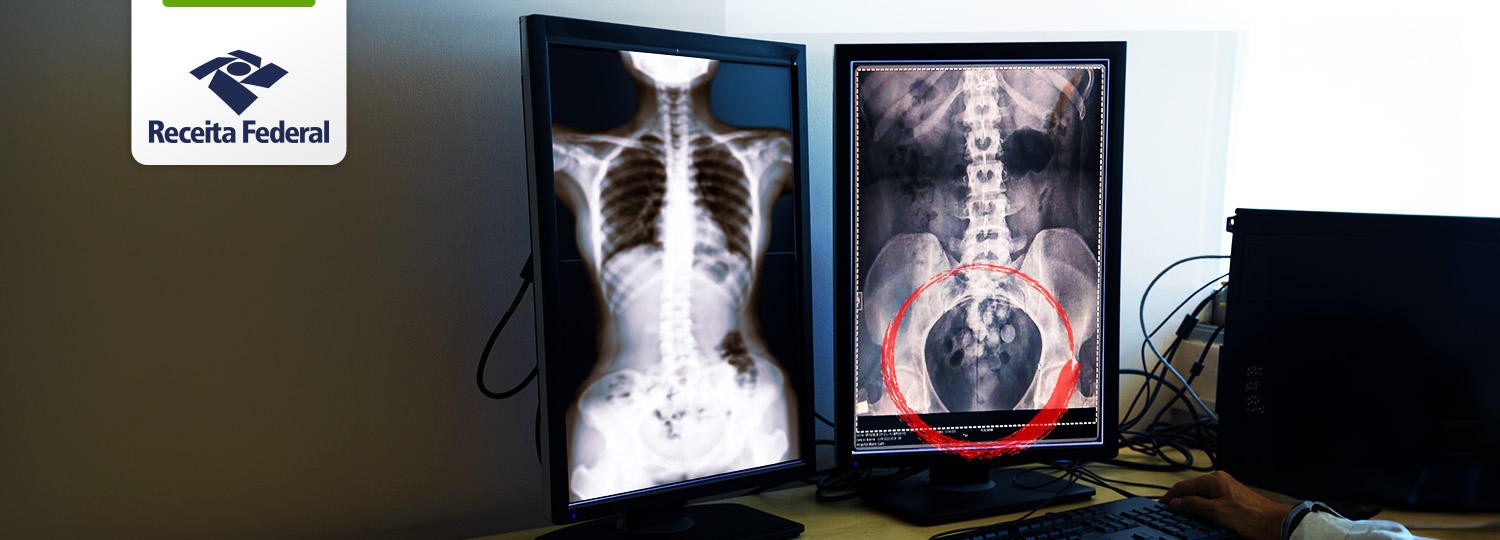

Você está aqui: Página Inicial Assuntos Notícias 2023 Setembro Receita Federal em Viracopos apreende aproximadamente 109 cápsulas de cocaína com passageira que embarcaria para Paris raiox.png